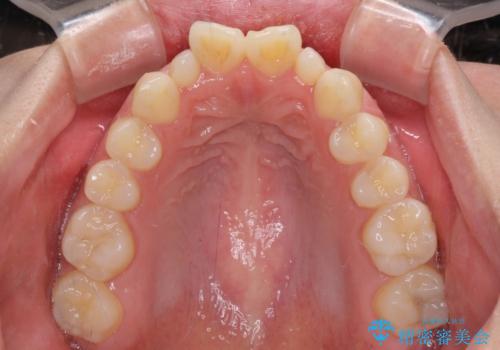

飛び出した前歯 インビザラインを用いた抜歯矯正治療

- 前方に飛び出した前歯を気にして来院された患者様です。

遠方の地元へ転居する予定があるとのことで、インビザラインによる治療を希望されていらっしゃいました。

上下前歯同士の距離が離れているため、上顎左右第一小臼歯2本を抜歯することで前突を改善することとしました。

しかしながら、左右ともに側切歯が矮小歯であるため、矯正治療で矮小歯前後にスペースを作り、矯正治療後にオールセラミッククラウンにて補綴治療を行うこととしました。